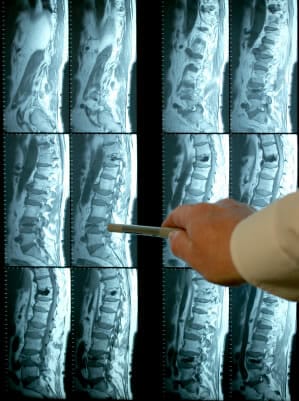

Low back pain is the most common condition I see, but do x-ray, CT and MRI results that show spondylosis and disc protrusion tell us much? Should you take their results as the be all and end all? Find out here.

This ultimately means advanced imaging such as MRI and CT scans are being used more and more.

There scans commonly pick up:

- Disk degeneration

- Facet joint hypertrophy

- Bone spurs

- Disc protrusion and more